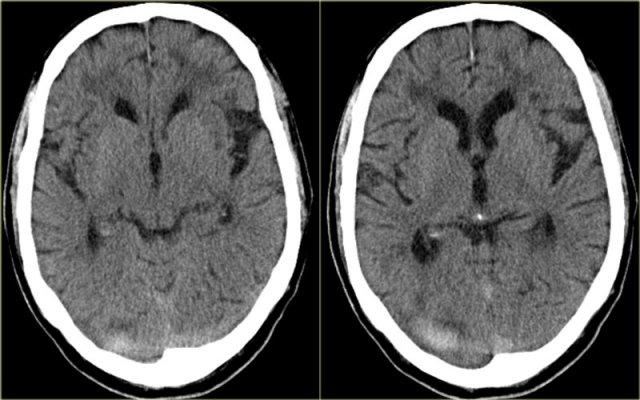

Nhồi máu tĩnh mạch (3) – Tĩnh mạch Labbe

Một dạng nhồi máu tĩnh mạch điển hình khác là do huyết khối tĩnh mạch Labbe.

Hình ảnh bên trái cho thấy giảm tỷ trọng ở chất trắng và ít rõ hơn ở chất xám của thùy thái dương trái.

Chẩn đoán phân biệt rộng bao gồm nhồi máu động mạch, nhiễm trùng, u não, v.v.

Lưu ý có một số đường tăng tỷ trọng trong vùng nhồi máu.

Đây là do xuất huyết.

Trong chẩn đoán phân biệt, cũng cần xem xét nhồi máu tĩnh mạch trong vùng phân bố của tĩnh mạch Labbe.

Tỷ trọng tăng nhẹ ở vùng xoang ngang trái (mũi tên) là chìa khóa để chẩn đoán.

Đây là dấu hiệu trực tiếp của huyết khối và bước tiếp theo là chụp CECT, xác nhận chẩn đoán (không hiển thị).